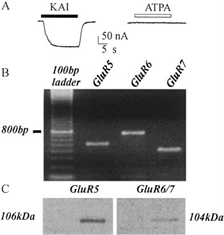

Leggi di Più..Espressione dei Recettori Neurotrasmettitoriali Umani

Lo studio introduce un modello innovativo per lo studio dell’epilessia,...